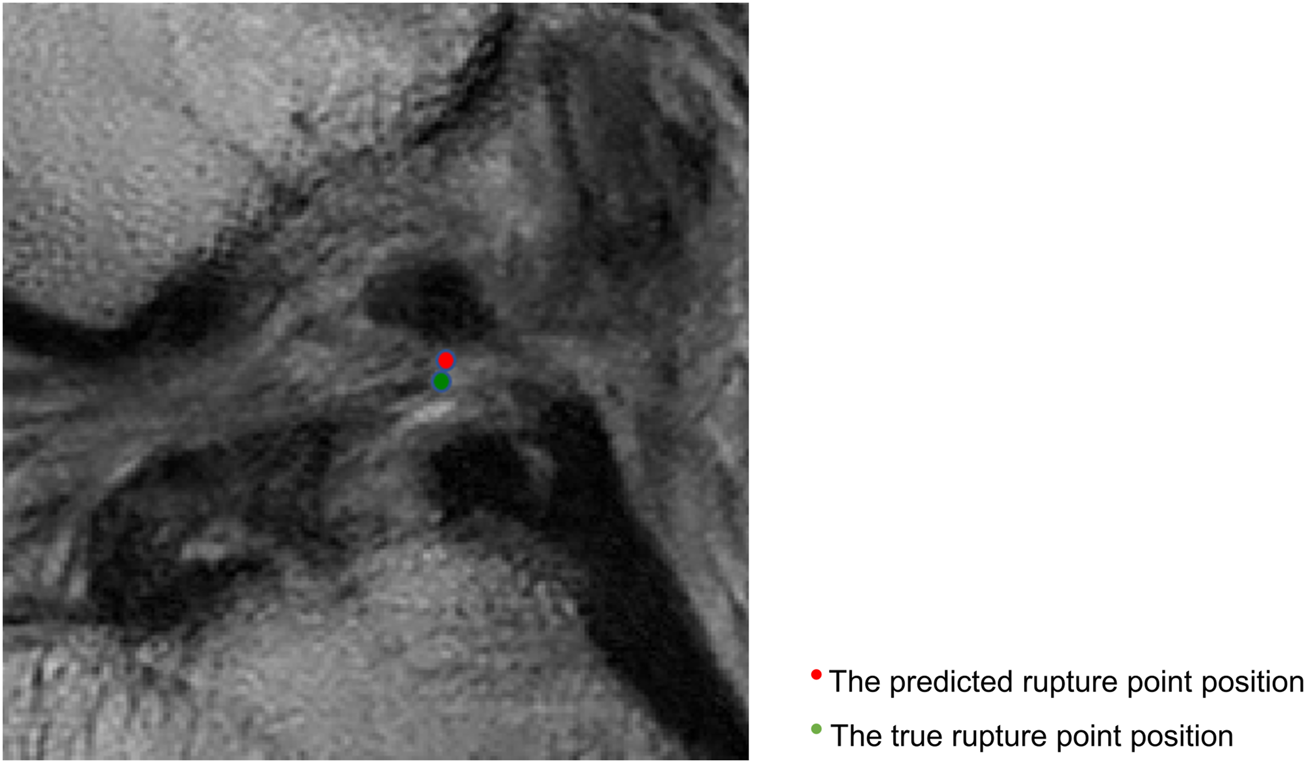

Figure 4 displays sagittal views of the cropped knee MR image, which were processed by the deep learning model for mislocalization and false classification. The true part of the rupture is on the middle side but the model outputs a classification result on the femoral side. The deep learning pipeline outputs incorrect localization results due to the Euclidean distance between the true and predicted rupture point locations being greater than 10 mm, which exceeds the maximum error threshold we set. Based on our model, the results of ACL rupture classification are directly related to the accuracy of its rupture localization, and incorrect localization leads to incorrect classification.

FIGURE 4. Sagittal views of the cropped MR image, mislocalization and false classification. The predicted rupture point is marked by red circle, while the true rupture point is green. The deep learning pipeline outputs incorrect localization results due to the Euclidean distance between the true and predicted rupture point locations being greater than 10 mm, which exceeds the maximum error threshold we set. A mislocalization resulted in a false classification. The true part of the rupture is the middle side, but the prediction is femoral side.